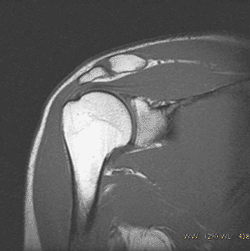

Kinematic MRI of the right shoulder

当院整形外科医、I.W先生の肩のMRIです。 段階的に腕を上げて撮像したMRI画像を、GIFアニメにして見ました。 |